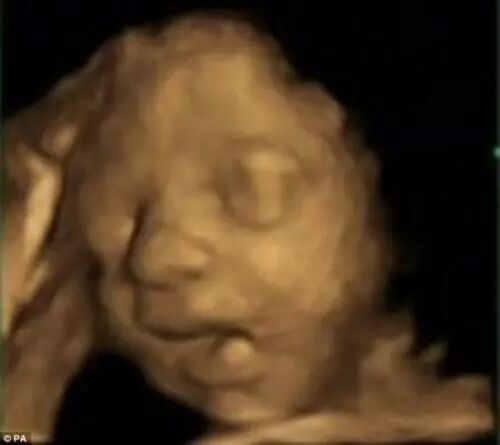

胎宝宝技能十:面部表情

通过观察胎儿的4D扫描,兰卡斯特大学的科学家们发现;24周,未出生的婴儿可以实现「二维」的表情,如微笑卷曲他们的嘴;36周,未出生的婴儿可以实现更复杂的面部表情,包括「痛苦」,例如皱起眉头,皱鼻子,嘟起小嘴。

(图片来源于网络)